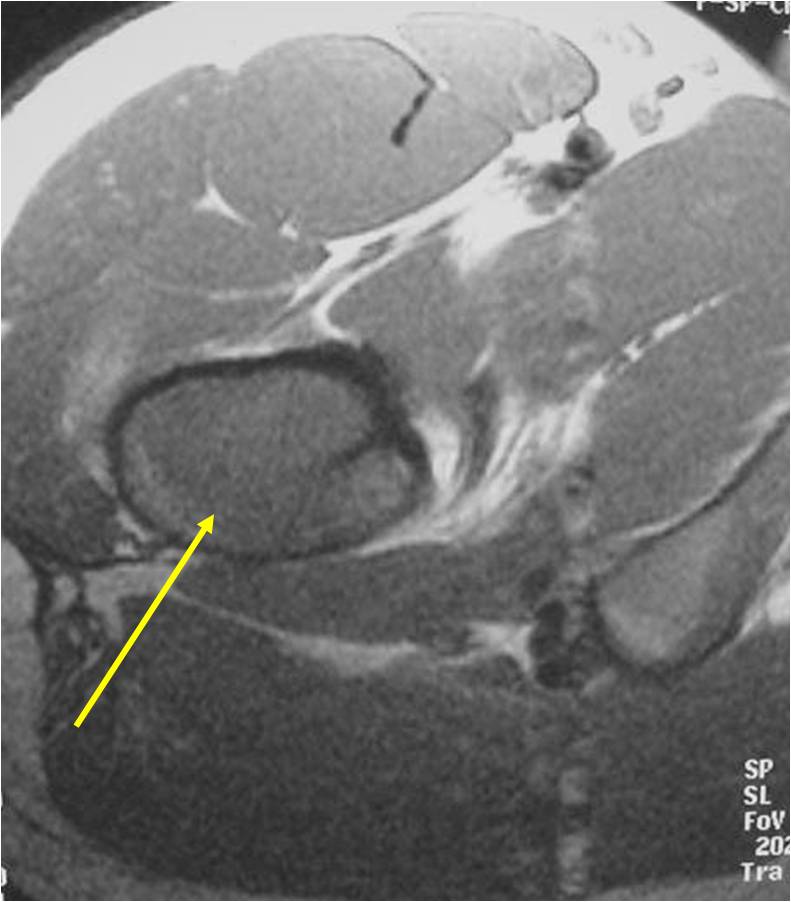

- Soft Tissue Mass in 90% of of cases

- Diffuse involvement of the medullary cavity is often obvious

- Ewing sarcoma is one of the most aggressive tumors

- High propensity for Local recurrences

- Distant metastases (predominantly in lungs and other bones)

- Lesions grossly confined to bone have a better prognosis than those with a soft tissue component